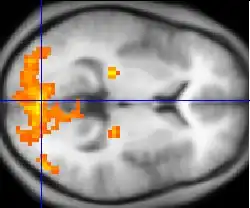

Dodatkowo wykorzystanie promieniotwórczych znaczników pozwala na obrazowanie procesów fizjologicznych organizmu. Przykładem może być tutaj zawierająca izotop radioaktywny glukoza. Po jej podaniu cukier zbiera się w tkankach o największym metabolizmie. Emitowane przez radioizotop pozytony mogą być rejestrowane w odpowiednim czujniku. W ten sposób da się określić miejsce, gdzie znajduje się ognisko raka lub stwierdzić, jakimi czynnościami zajmuje się w tej chwili kresomózgowie pacjenta.

Najpopularniejsze metody diagnostyki medycznej oparte na technice jądrowej:

- tomografia komputerowa osiowa (ang. computed tomography, CT, computed axial tomography, CAT),

- tomografia komputerowa wysokiej rozdzielczości (ang. high resolution computed tomography, HRCT),

- spiralna tomografia komputerowa (ang. spiral computed tomography, sCT),

- magnetyczny rezonans jądrowy (ang. nuclear magnetic resonance NMR, magnetic resonanse imaging, MRI),

- pozytonowa tomografia emisyjna (ang. positron emission tomography, PET).

Wykorzystanie wszystkich tych technik pozwala na szybkie i precyzyjne diagnozowanie wielu poważnych uszkodzeń organów wewnętrznych. Obserwacja fizjologii ludzkiego ciała przyczynia się też do postępu w badaniach nad człowiekiem. Dzięki możliwości „podglądania” ludzkiego mózgu podczas pracy naukowcy stają o krok bliżej do zrozumienia fenomenu inteligencji. Z wyjątkiem magnetycznego rezonansu jądrowego każda z technik radiologicznych wiąże się z napromieniowaniem pacjenta. Oznacza to, że w przypadku kumulacji dawki promieniowania jonizującego mogą pojawić się skutki uboczne. Istnienie tych skutków ubocznych nie może być bagatelizowane, ale obecnie przeważa strach przed każdym rodzajem promieniowania nawet w najmniejszych dawkach, które są używane w diagnostyce.